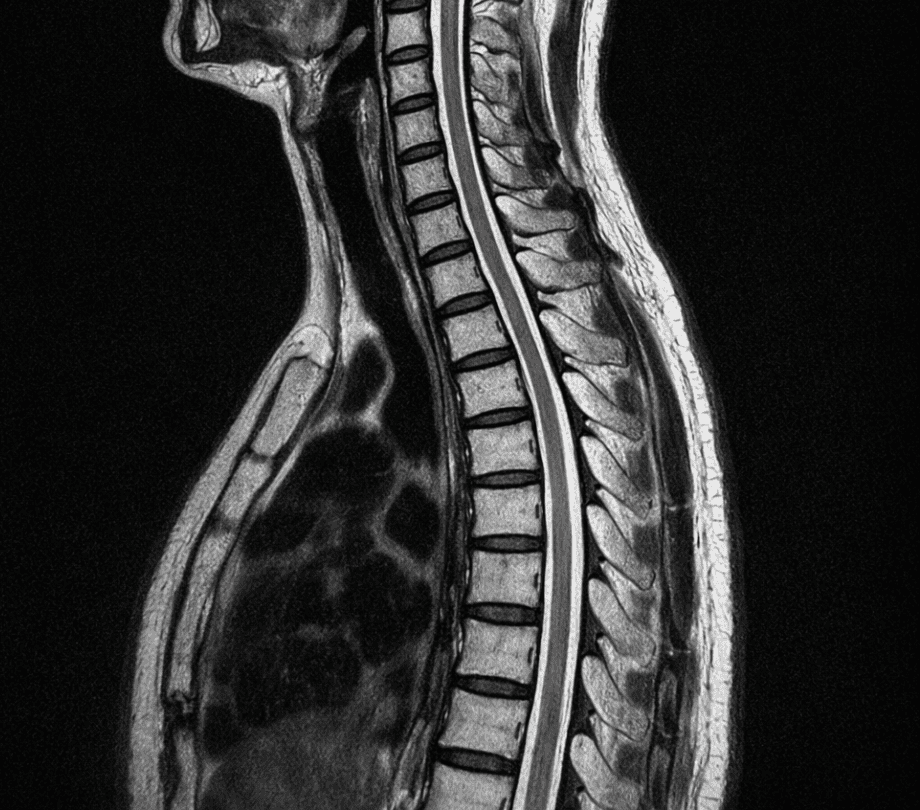

Spine and Musculoskeletal Imaging

We offer comprehensive imaging of the spine and musculoskeletal system, aiding in the diagnosis of back pain, joint injuries, and arthritis. Our scans are detailed and accurate.